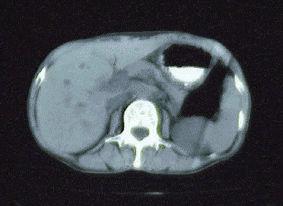

Diffuse inflammatory gastric disease resembling scirrhous advanced stomach cancer.

female

65-69

Inflammatory or ulcerative disease / lesions/Others

Stomach/More than one of above

CT